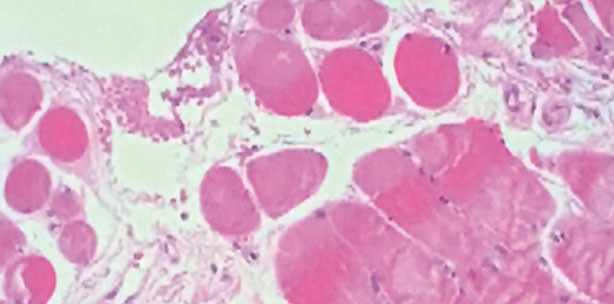

Bei einer leukoplakischen, exophytisch wachsenden Veränderung am linken Zungenrand zeigt die Histologie nach dem Einsatz der Hochfrequenz (2,2MHz) geringe thermische Veränderungen in der quergestreiften Muskulatur (Abb. 3), die thermische Reaktionsschicht im Stroma ist sehr gering, es ist keine Vakuolenbildung zu sehen. Abbildung 4 zeigt ein histologisches Vergleichsbild der thermischen Reaktionszone eines Exzidates, welches mit einem 980-nm-Laser genommen wurde. Erkennbar ist die sehr viel breitere und partiell verschmolzene Reaktionszone infolge einer erheblichen Temperatureinwirkung.